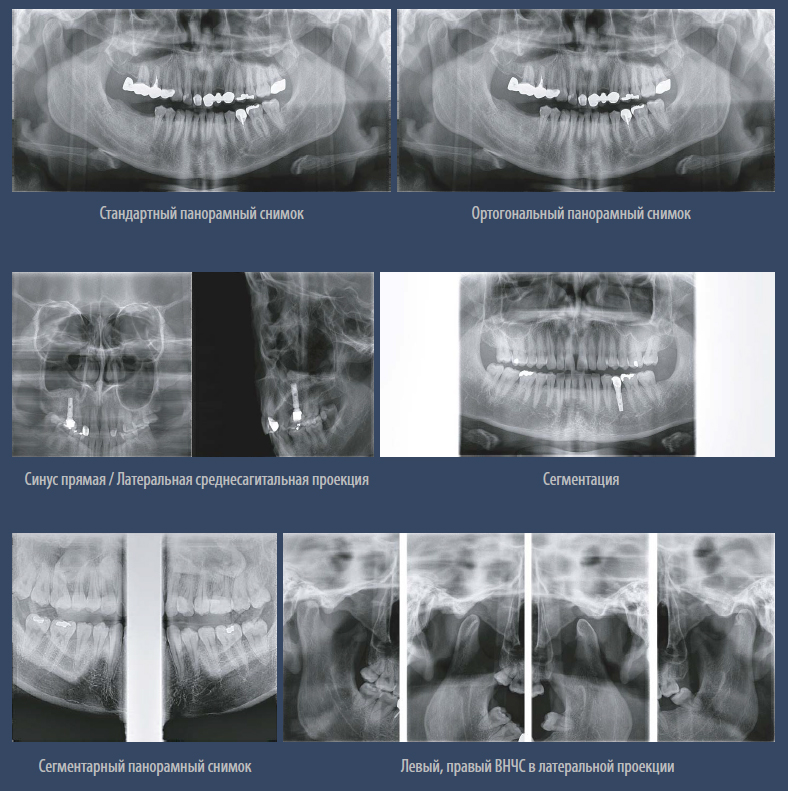

Панорама

Высокое разрешение при панорамной съёмке.

Мульти фокус.

Функция используется в режиме панорамы. Технология мульти фокуса позволяет добиться максимального качества, максимальной глубины резкости и захвата всей зоны сканирования при помощи пяти фокусных слоев.

Режимы экспозиции панорамной съёмки.

– Стандартный панорамный

– Ортогональный панорамный

– Сегментарный панорамный

– Горизонтальные и вертикальные сегменты

– Прямая проекция ВНЧС

– Детский панорамный

– Левый, правый ВНЧС в латеральной проекции

– Левый, правый ВНЧС прямая и латеральная проекции

– Синусы латеральная и прямая проекции

Режимы экспозиции.jpg